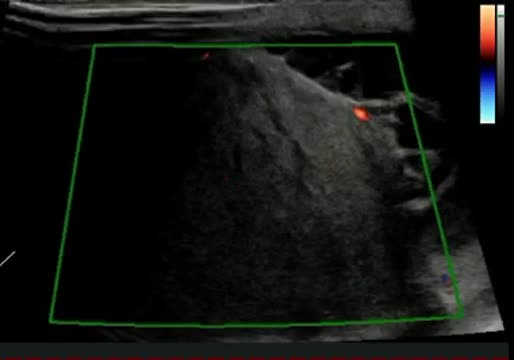

La mayoría de las veces, el seminoma se encuentra confinado al interior de la túnica albugínea. Suele presentarse ecográficamente como una lesión homogénea, hipoecogénica e intratesticular, de aspecto numular. Ocasionalmente es multinodular (vídeo 1) o se presenta como una lesión focal con márgenes lobulados (figs. 2a y b).

Cortes longitudinales de masas testiculares: a) Masa intratesticular homogénea e hipoecogénica (medida en ejes longitudinal y anteroposterior con línea discontinua amarilla) con diagnóstico anatomopatológico de seminoma; b) Imagen a con captación Doppler color; c) Masa que ocupa la práctica totalidad del teste (medido en ejes longitudinal y anteroposterior con línea discontinua amarilla) hipoecogénica con diagnóstico anatomopatológico de linfoma.